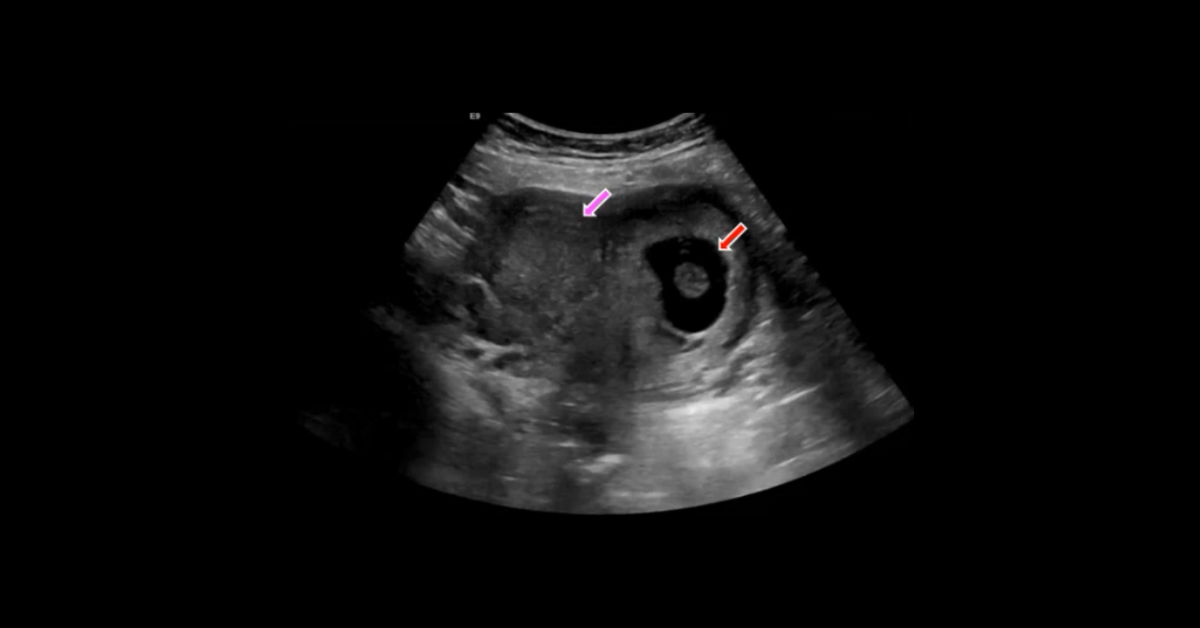

Presented by Vincent Mellnick, MD at Practical Radiology 2025. The upper gastrointestinal tract can be oft-overlooked site of disease in the emergency department patient, but is frequently be the site of pathology, including inflammation/infection, ischemia, obstruction, perforation, and hemorrhage. This talk will discuss common (and some uncommon) conditions causing these presentations in the esophagus, stomach, and duodenum, with emphasis on CT findings.